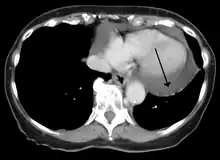

A CT scan showing a pericardial effusion

Cardiac CT and MRI scans: cross-sectional imaging with computed tomography (CT) can help localize and quantify the effusion, especially in a loculated effusion (an effusion contained to one area).[12] CT imaging also helps assess for pericardial pathology (pericardial thickening, constrictive pericarditis, malignancy-associated pericarditis).[1] Whereas cardiac MRI is reserved for patients with poor echocardiogram findings and for assessing pericardial inflammation, especially for patients with continued inflammation despite treatment.[5] CT and MRI imaging can also be used for continued follow up on patients.

Pericardial effusion due to malignancy. Note bulbous heart and primary lung cancer in right upper lobe.